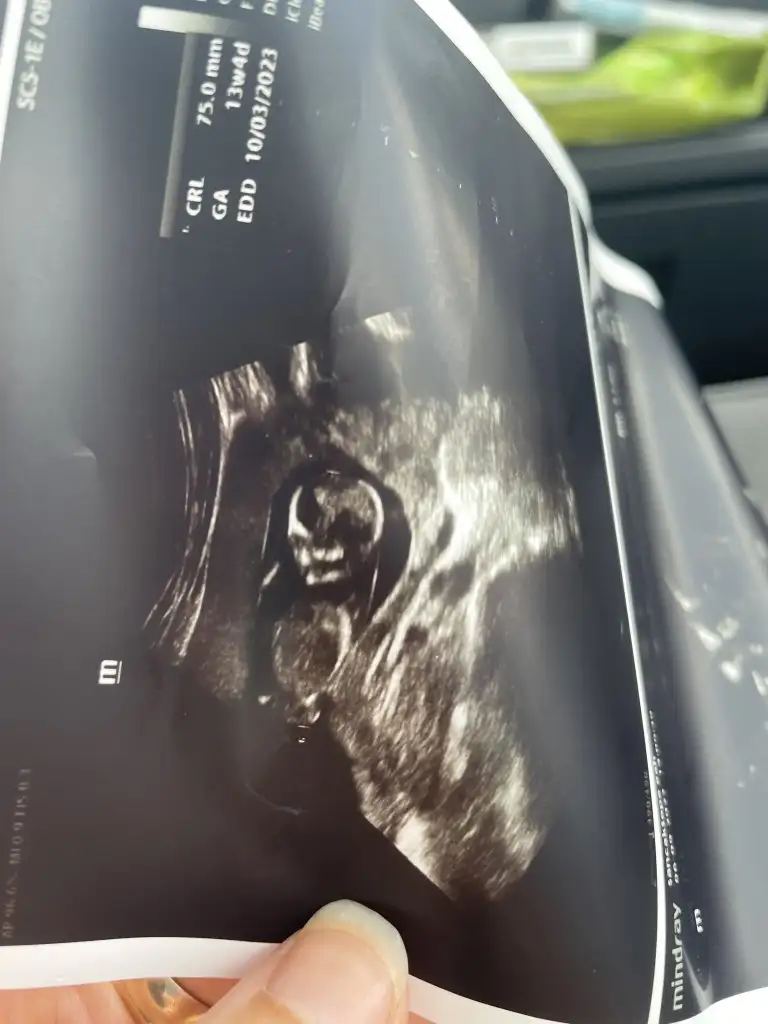

Hayırlı olsun canımKıza benziyoruz ama net söylemiyoruz klitoris gördüm gibi ama Net olması için 16. Hafta dedi doktorumuz ; ense kalınlığı burun iyi görünüyor test sonucu 2 hafta sonra

ultrason görüntüsü varmı :)Kıza benziyoruz ama net söylemiyoruz klitoris gördüm gibi ama Net olması için 16. Hafta dedi doktorumuz ; ense kalınlığı burun iyi görünüyor test sonucu 2 hafta sonra